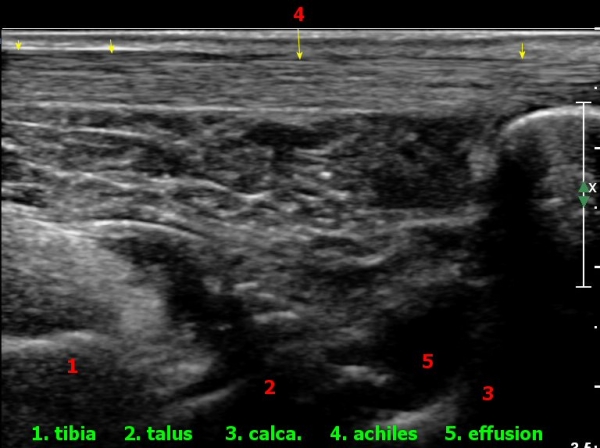

ÃÊÀ½ÆÄ°Ë»ç : ¹ß¸ñ °üÀý Á¾´Ü¸é°Ë»ç¿¡¼­ ¹ß¸ñ °Å°ñ ¿¬°ñÀÌ ¾ã¾îÁ®(thinning) º¸ÀδÙ(»çÁø 1).

Àü°ÅºñÀδë Á¾´Ü¸é°Ë»ç»ó Àü°ÅºñÀδëÀÇ Àú¿¡ÄÚ À§Ãà°ú Á·±Ùµ¿(sinus tarsi) ¼ö¾×Àú·ù°¡

°üÂûµÈ´Ù(»çÁø 2, 3).